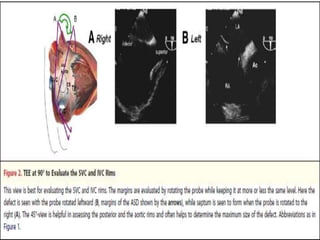

Bicaval view SVC & IVC Rims

Aortic rim (down) Posterior rim(UP)

 Trans catheterclosure of ASD is an effective alternative to surgery in most patients with ostium secundum ASD.  Factors that decide suitability for trans catheter closure include size of the defect and presence of adequate tissue rims around the defect.  Accurate imaging of the anatomic features of the ASD is critical for case selection, planning, and guidance during the procedure.

• 93.

 The rimsof a secundum ASD are labeled as - 1. Aortic or (anterosuperior), 2. Atrio ventricular (AV) Valve ,mitral or (inferoanterior), 3. Superior vena caval (SVC or posterosuperior), 4. Inferior vena caval (IVC or posteroinferior) 5. Posterior or superrior 6. Coronary sinus By conventional definition, a margin 5 mm is considered to be adequate.Deficient aortic rim (42.1%).